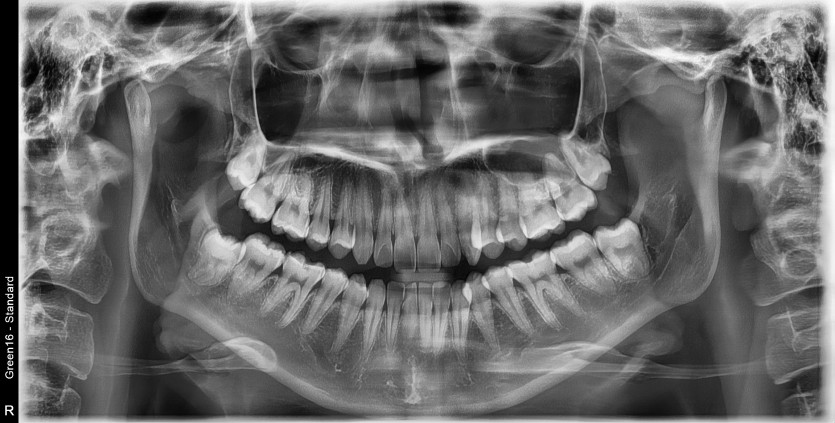

#38 사랑니 발치

구강외과 전문의가 당일 발치했습니다.